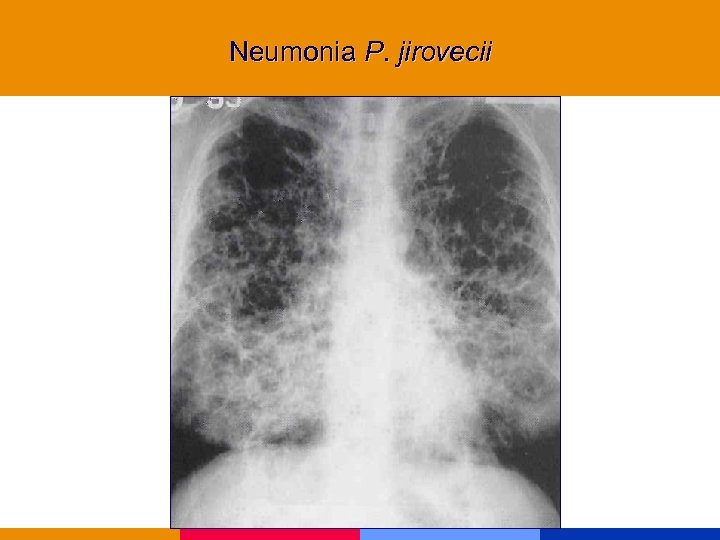

Neumonía por Pneumocistis jirovecii

Neumonía por Pneumocistis jirovecii

Neumonía por Pneumocistis jirovecii § CD 4 < 200 mm 3 § Comienzo insidioso: fiebre, tos seca, disnea. Hallazgos al examen físico incaracterísticos. § Lab: VSG: 50 mm. LDH, valor diagnóstico y pronóstico. Hipoxemia. § Rx infiltrado intersticial difuso, neumatocele, neumotórax. § TC de alta resolución.

Neumonía por Pneumocistis jirovecii § CD 4 < 200 mm 3 § Comienzo insidioso: fiebre, tos seca, disnea. Hallazgos al examen físico incaracterísticos. § Lab: VSG: 50 mm. LDH, valor diagnóstico y pronóstico. Hipoxemia. § Rx infiltrado intersticial difuso, neumatocele, neumotórax. § TC de alta resolución.

Neumonia P. jirovecii

Neumonia P. jirovecii

Neumonia P. jirovecii

Neumonia P. jirovecii

Neumonia P. jirovecii

Neumonia P. jirovecii

Neumonia P. jirovecii

Neumonia P. jirovecii

Neumonia P. jirovecii

Neumonia P. jirovecii

Neumonia P. jirovecii

Neumonia P. jirovecii

Neumonia P. jirovecii

Neumonia P. jirovecii